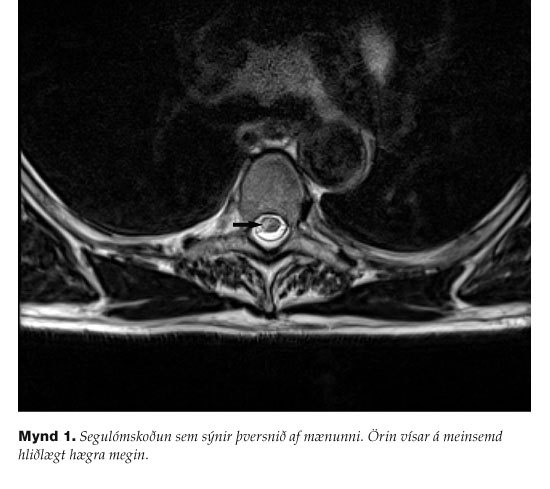

Í framhaldi af taugaskoðun þótti rétt að útiloka meinsemd í framheila vinstra megin (hreyfisvæði ganglims gagnstæðrar hliðar) vegna einangraðrar lömunar í hægri ganglim. Tölvusneiðmyndarannsókn af heila gaf engar vísbendingar um ferskt drep eða blæðingu. Þá vaknaði grunur um drep í mænu. Segulómrannsókn leiddi í ljós segulskynsbreytingar hægra megin í mænu, greinilegast í hæð við brjóstliðbol 4 (mynd 1). Síðar var gerð Holter-rannsókn og ómun af hjarta og voru rannsóknaniðurstöður eðlilegar.

Veikindi sjúklings í þessu tilfelli einkenndust af skyndilegu upphafi með afar sárum verk í miðjum brjóstkassa í hæð við 4. brjóstliðbol. Verkinn lagði fljótlega umhverfis brjóstkassann. Í kjölfarið, á fyrstu klukkustundunum, gætti vaxandi máttminnkunar í hægri ganglim og síðar kom í ljós skert starfsemi þvagblöðru. Skyneinkenni voru ekki til staðar. Sjúklingurinn var fyrst grunaður um brátt hjartadrep eða flysjun í ósæð. Þegar máttminnkun í ganglim var staðfest við taugaskoðun beindist athygli að miðtaugakerfinu. Fyrst var útilokuð bráð skemmd á svæði framheilaslagæðar vinstra megin. Þegar tölvusneiðmynd af höfði var eðlileg vaknaði grunur um mænueinkenni í hæð við 4. brjóstliðbol. Sýnt þótti út frá klínískum einkennum að mænudrepið væri aftarlega í hliðlægum heila- og mænubrautum (lateral corticospinal tract) þar sem hreyfitaugaþræðir til ganglims liggja. Þetta svæði er nært af aftari strengs slagæðinni (posterior funicular) sem er grein frá aftari mænuslagæðinni (posterior spinal artery). Segulómrannsókn sýndi segulskynsbreytingar hægra megin í mænu í hæð við 4. brjóstliðbol, breytingarnar eru ekki skýrt afmarkaðar. Drep á svæði aftari blóðveitunnar í mænunni eru mun sjaldgæfari en á fremra svæðinu. Batahorfur eru þó almennt taldar betri. Í okkar tilfelli hafði sjúklingur tiltölulega lítil brottfallseinkenni í upphafi. Þrátt fyrir ítarlegar rannsóknir fannst ekki sértæk skýring á mænudrepi.